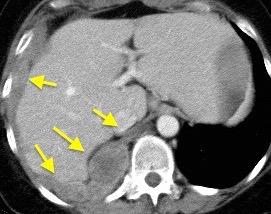

T. mixto de células germinales del testículo izquierdo

Nódulos pulmonares múltiples. (flechas verdes). Masas paratraqueales. (flechas amarillas). Dudoso ensanchamiento retrocrural (flechas negras). sigue….

Ttawfik A et al. Trans-diaphragmatic Pathologies: Anatomical Background and Spread of Disease on cross-sectional Imaging. Current Problems in Diagnostic Radiology. 2021.

T. mixto de células germinales del testículo

izquierdo Metástasis pulmonares. (flechas verdes). Ganglios paratraqueales. (flechas amarillas). Ganglios retroperitoneales (flechas negras)

Tawfik A et al. Trans-diaphragmatic Pathologies: Anatomical Background and Spread of Disease on cross-sectional Imaging. Current Problems in Diagnostic Radiology. 2021.